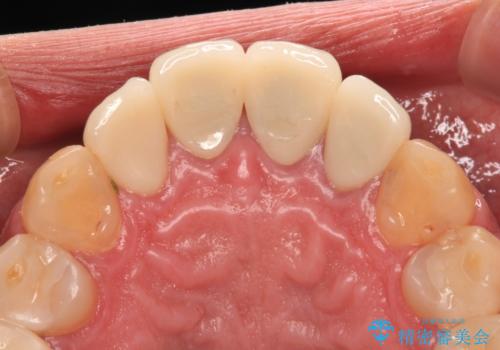

- 黄ばんだ前歯や目立つ奥歯の銀歯をきれいにしたいとのことで来院された患者様です。

小さい修復物の銀歯が装着されている歯はセラミックインレーにて、その他はオールセラミッククラウンにて補綴治療を進めることとしました。